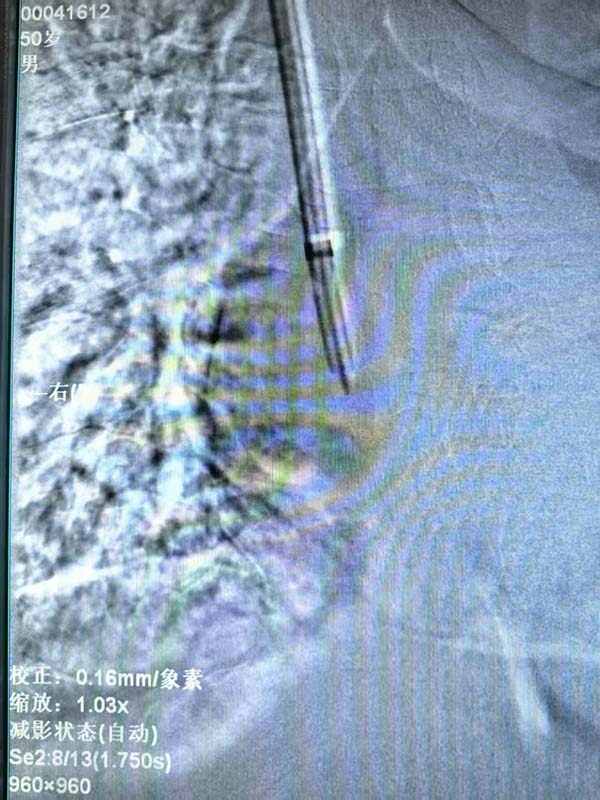

该项手术由我院安宁疗护一科曲伟主任主刀,术前仔细评估患者一般情况及血管情况,制定手术方案,手术全程在导管室进行,术中实时监测血流动力学指标,超声引导下通过精准的静脉解剖定位置入导管,术中X线定位下将导管撕脱鞘送入颈内静脉至上腔静脉-右心房交界处,位置满意后予以固定。